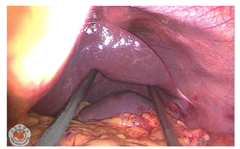

患者女,40岁,身高160 cm,体质量52 kg,因2 d前无明显诱因出现左下腹部持续性绞痛,于2018年10月19日急诊入院,体温37.7℃,脉搏112次/分,伴稍恶心,无呕吐、放射痛、发热,无腹泻、血便,无尿频、尿痛等症状。1 d前曾在当地社区医院以"急性肠炎"给予抗感染、解痉等治疗,自觉症状有所缓解,次日午间症状再次加重。查体:左下腹压痛(+)、反跳痛(+),局部腹肌紧张明显。行腹部CT平扫检查示:结肠走行反位,右半结肠位于左上腹,阑尾增粗伴周围渗出,周围间隙模糊,阑尾最粗约1.7 cm,临近盲肠壁稍增厚;胃腔大部分位于右侧,十二指肠垂直下行,可见Ladd束带;肝脏体积明显增大;脾脏受推挤,位于左侧肾上腺前方(图1,图2,图3)。诊断为"结肠反位,阑尾炎累及盲肠"。血常规检查示:白细胞计数8.81×109/L,中性粒细胞百分比79.5%。综合各项检查结果,诊断为"急性肠旋转不良型左侧阑尾炎",遂于当夜急诊行腹腔镜下异位阑尾切除术。腔镜探查示盆腔内大量积脓,大网膜覆盖左侧回盲部,乙状结肠位于盆腔右侧,肝左叶明显增大并覆盖脾脏,胆囊仍位于右侧,切除阑尾及网膜组织大小约8.0 cm×6.0 cm×2.5 cm(图4,图5,图6,图7)。

手术过程顺利,次日进食,排气、排便恢复良好。于术后第3日拔出盆腔引流管后出院,术后病理回报:(阑尾)切除标本,阑尾长4 cm,直径0.5~0.8 cm。(1)急性阑尾炎伴周围组织及系膜急性炎;(2)急性腹膜炎。出院时Trocar穿刺口及引流管口无感染征象,血常规无异常。术后1周门诊复查,患者无发热,自觉腹部无明显疼痛,排便正常。查体:脐上及左下腹可见3处Trocar穿刺口瘢痕,愈合好,无红肿渗出。全腹软,无明显压痛及反跳痛,全腹未及明显包块。右下腹听诊肠鸣音正常,4次/分。血常规及肝、肾功能检查未见明显异常。

此病例可充分体现腹腔镜阑尾切除术优势所在:相对于传统麦氏切口阑尾切除术,腹腔镜阑尾切除术具有视野广阔的特点,不易漏诊。此患者如行开腹手术,由于回盲部位置较高,反麦氏切口操作可能较困难,左侧探查口或正中切口则创面较大,影响术后恢复及美观。患者经腹腔镜阑尾切除手术后,腹痛及发热症状缓解,术后1周复查时Trocar穿刺口愈合良好,肠蠕动功能恢复良好。